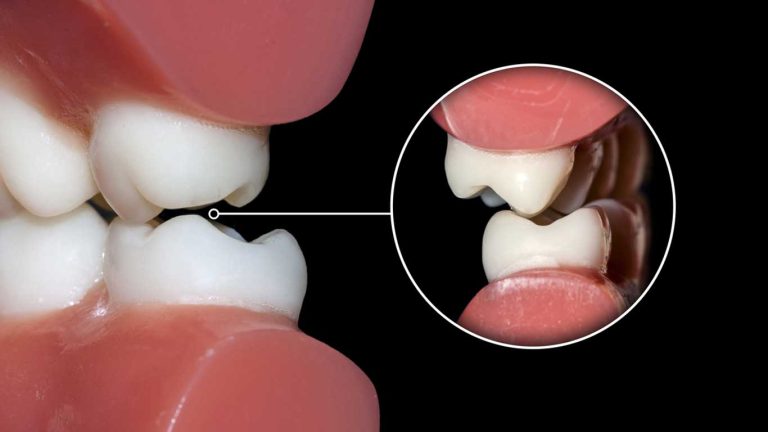

تحلیل لثه در ارتودنسی به معنای از دست رفتن و پسروی بافت لثه از اطراف دندان ها در طول دوره درمان با دستگاه های ارتودنسی است. این وضعیت باعث می شود که بخشی از ریشه دندان که به طور طبیعی باید توسط لثه و استخوان پوشیده باشد، در معرض محیط دهان قرار گیرد. این یک نگرانی جدی است زیرا ریشه دندان فاقد لایه محافظ مینا بوده و بسیار نرم تر از تاج دندان است. نمایان شدن ریشه، دندان را در برابر حساسیت شدید به سرما و گرما، سایش و به خصوص پوسیدگی ریشه، بسیار آسیب پذیر می کند.

این مشکل نه تنها سلامت دندان را به خطر می اندازد، بلکه بر زیبایی لبخند نیز تاثیر منفی می گذارد. دندان هایی که دچار تحلیل لثه شده اند، بلندتر از حد طبیعی به نظر می رسند و ممکن است فاصله های تیره ای بین آن ها ایجاد شود. عامل اصلی این فرآیند، التهاب لثه در ارتودنسی است. اگر پلاک باکتریایی به طور موثر از اطراف بریس ها تمیز نشود، التهاب مداوم می تواند منجر به تخریب بافت های نگهدارنده دندان، از جمله لثه و استخوان شود.

- موقعیت اولیه نامناسب دندان ها: دندان هایی که از ابتدا در خارج از قوس استخوانی قرار دارند، مانند دندان های بیرون زده، با یک لایه استخوانی نازک پوشیده شده اند و مستعد تحلیل هستند.

- حرکات ارتودنسی پر خطر: حرکت دادن دندان ها به میزان زیاد به سمت بیرون (گونه یا لب) می تواند ریشه دندان را از پوشش استخوانی خارج کرده و باعث تحلیل لثه شود.